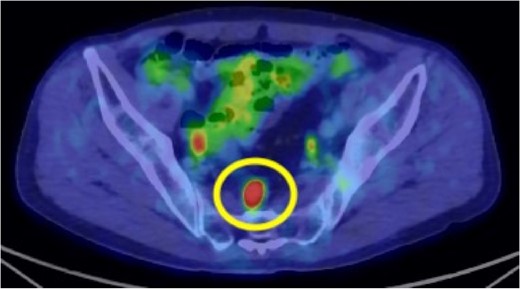

A 72-year-old man diagnosed with NSCLC was referred for possible surgical treatment of a solitary nodule detected in the mesorectum. His medical history included hypertension and endoscopic resection of colonic polyps, with no prior thromboembolism. He had received combined medical treatment for NSCLC (cT4N0M0, stage IIIA) (Fig. 1), including four courses of cisplatin and docetaxel chemotherapy with a 60 Gy/30 fractions radiation dose, followed by 1 year of consolidation therapy with durvalumab (640 mg/body). The patient tolerated the treatment well, achieving a complete response 13 months before presentation (Fig. 2). However, the mesorectal nodule was incidentally discovered during surveillance CT after NSCLC treatment completion. It was round, 15 mm in diameter, showed contrast enhancement, and was near the mesorectal vessels (Fig. 3a and b). An FDG PET/CT scan revealed a solitary mesorectal nodule with an SUVmax of 10.3 (Fig. 4). Consequently, the radiologist suggested differential diagnoses of malignant lymphoma and metastatic lymph nodes from the urinary or lower gastrointestinal tract, as NSCLC typically does not metastasize to mesorectal lymph nodes. No other abnormal FDG uptake was observed. Laboratory tests showed normal levels for tumor markers, including carcinoembryonic antigen, sialyl Lewis X (SLX), squamous cell carcinoma antigen, neuron-specific enolase, cytokeratin fragment (CYFRA), progastrin-releasing peptide, and blood coagulability was within the normal range. Total colonoscopy revealed no neoplastic lesions, and urinary cytology showed nonmalignant urothelial cells. Noninvasive diagnostic approaches, including endoscopic or CT-guided biopsy, were extensively discussed but deemed difficult because of anatomical restrictions, risk of dissemination, and procedure-related complications (such as bleeding or perforation). Because of the potential malignancy and need for en-bloc resection, we opted for surgical resection using a standardized laparoscopically assisted mesorectal excision technique. During rectal dissection, the nodule was not visible through the posterior and lateral sides because it was completely embedded in the mesorectum. Therefore, a Pfannenstiel incision was made in the lower abdomen to exteriorize the rectum after the division of the proximal colon. The nodule was confirmed by direct palpation, marked with a stitch, and subsequently removed after intracorporeal transection of the distal rectum. We inspected the resected specimen and confirmed that the nodule was incorporated (Fig. 5a and b). A colorectal anastomosis was then performed using a double-stapling technique with a circular stapler. The postoperative course was uneventful, except for a slight elevation of the d-dimer level (up to 3.26 μg/ml) on postoperative Day 7, which normalized spontaneously without intensive anticoagulation therapy. The patient was discharged on postoperative Day 10. Pathological examination revealed that the 7-mm white nodule was an intravenous organized thrombus in the mesorectum surrounded by granulation tissue, with no malignancy observed (Fig. 6a and b). Postoperatively, the patient did not require additional chemotherapy or anticoagulation therapy. During the 16-month follow-up, no radiological evidence of NSCLC recurrence and thromboembolism was detected (Fig. 7).

Preoperative 18F-fluorodeoxyglucose (FDG) positron emission tomography (PET)/computed tomography (CT) image. The circle highlights the nodule located in the mesorectum with a maximum standardized uptake value (SUVmax) of 10.3.

FDG PET/CT is widely used for clinical staging of malignancy and detecting postoperative recurrence due to its ability to provide relevant metabolic information. It is well-known that SUVmax is higher for malignant lesions compared to benign ones, reflecting their active glucose metabolism. A previous study showed that FDG PET/CT has good diagnostic performance for staging distant metastasis in patients with NSCLC [7]. Additionally, SUVmax is useful for diagnosing venous thromboembolism (VTE) [8]. Several studies have demonstrated the efficacy of FDG PET/CT in distinguishing venous tumor thrombus from venous bland thrombus. Hu et al. [9] reported that tumor embolisms associated with portal vein thrombosis had a significantly higher SUVmax than simple thrombi, with tumor embolisms showing an SUVmax of 6.37 ± 2.67 and simple thrombi showing an SUVmax of 2.87 ± 1.47. Similar results were found in studies on renal cell carcinoma and hepatocellular carcinoma [10–12]. In our present case, the SUVmax of the mesorectal nodule was 10.3, which reasonably led to suspicion of malignancy.

The underlying mechanism of the solitary mesorectal thromboembolism in this case remains unclear. Patients with malignant diseases are at high risk for VTE, and cancer-associated thrombosis is a major complication among patients with lung cancer [13]. The risk of cancer-associated thrombosis is influenced by patient and cancer characteristics. For instance, conditions such as anemia, chronic obstructive pulmonary disease, and obesity can increase the risk of VTE [14]. Additionally, chemotherapy is an independent risk factor for VTE in patients with lung cancer [13]. A large retrospective study published in 2011 reported that 18.1% of patients treated with cisplatin-based chemotherapy experienced thromboembolic events during treatment or within 4 weeks of the last treatment dose [15]. While our patient did not have comorbidities associated with risk factors for VTE, we posit that cisplatin-based chemotherapy might have contributed to the development of thromboembolism. To the best of our knowledge, no previous studies have reported solitary thromboembolism in the mesorectum. Notably, given the high SUVmax of the nodule during FDG PET/CT, it was challenging to rule out malignancy in our case.